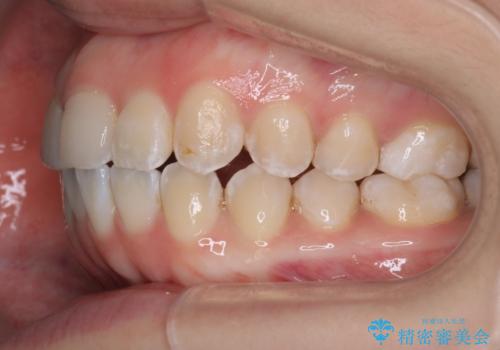

「フルリンガル矯正|アンカースクリューを活用し正中を整えた症例」

- 他院で矯正治療を受けていた患者様が、より理想的な仕上がりを求めて転院されました。主なお悩みは正中(前歯の中心)がズレていることで、歯並び全体をきれいに整えたいとのご希望でした。治療には舌側(裏側)に装置を装着するフルリンガル矯正を採用し、さらにアンカースクリューを用いて奥歯を後方へ移動(遠心移動)させることでスペースを確保し、正中を調整する計画を立てました。

矯正装置を装着し、アンカースクリューを活用しながら奥歯を少しずつ後ろへ動かし、正中を整えていきました。治療には時間がかかりましたが、計画通りに歯を移動させ、バランスの取れた歯並びへと仕上げることができました。裏側矯正のため、見た目を気にすることなく治療を進められた点も、患者様にとって大きなメリットでした。治療後は、「正中がしっかり合って、口元がスッキリした」とご満足いただきました。